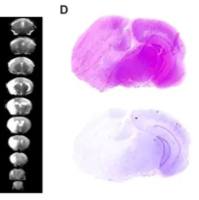

文献和实验采用不同的抗原引入途径改变免疫应答格局 对实验变态反应性脑脊髓炎(EAE)实施免疫干预的策略。EAE是下面即将提到的多发性硬化症的动物模型。如果用自身抗原髓鞘碱性蛋白(MBP)的一个衍生肽加入佐剂后免疫小鼠,近10d后,动物开始出现EAE症状,然后病情逐渐加重。如果先用抗原肽作雾化吸人,再行免疫,发现疾病的严重程度明显缓解。说明抗原吸人预处理,负向调变了同一抗原随后诱发的自身免疫病。其确切机制未明,估计和雾化吸人抗原肽后可通过黏膜免疫系统诱导调节